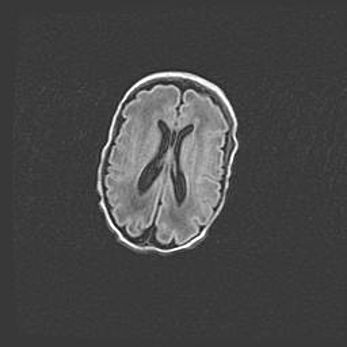

Лейкомаляция с кистозно-глиозной дегенерацией головного мозга.

Возраст: 2 месяца 25 дней

Вес: 6400 г

Окружность головы: 40 см

Срок гестации: 41 неделя

Лейкомаляцию относят к ишемически-гипоксическим повреждениям головного мозга, диагностируемым у новорожденных. При лейкомаляции в головном мозге обнаруживают очаги некроза, возникшие после тяжелой гипоксии и нарушения кровотока. В процессе морфогенеза очаги проходят три стадии: 1) развития некроза, 2) резорбции и 3) формирования глиозного рубца или кисты. Перивентрикулярная лейкомаляция (ПЛ) встречается примерно в 12% случаев среди новорожденных, обычно – у недоношенных детей, причем, частота ее зависит от массы, с которой младенец появился на свет. Наибольшее число малышей страдает лейкомаляцией, если масса при рождении 1500-2500 г.